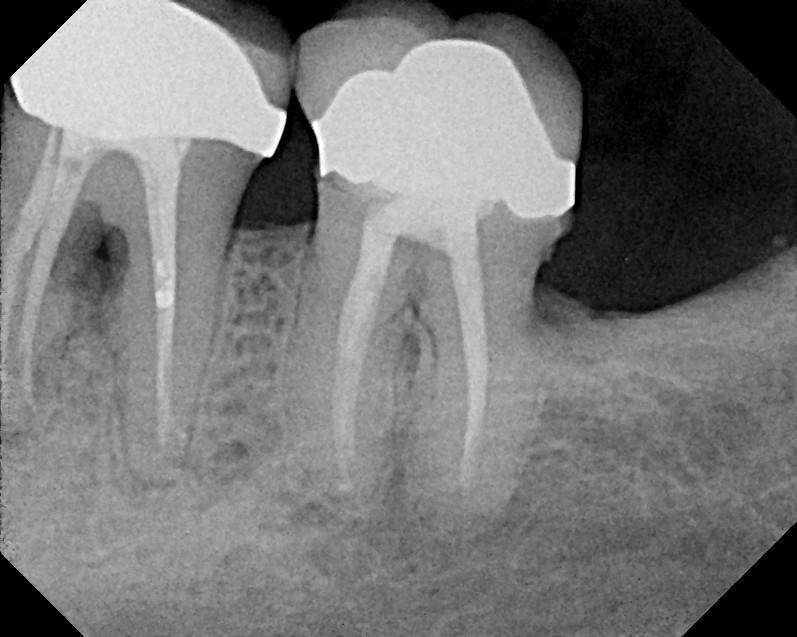

Most certainly in the ground, but only after you separate your human body from the dead body in your mouth, your root cadavers. These you see here are routine pictures of dead teeth:

The pathological tissues such as granuloma, cysts, abscesses, marked acute/chronic inflammation, and necrotic bone, to name a few, are the drainage field of the septic tooth. Nature attempts to prevent toxic dissemination throughout the full biome thus insuring its health, hopefully.

A septic tank analogy is valid here in that the dead tooth or dental implant is a reservoir for corrupt matter and their liquids and gases, leaking out into the underlying bone, lymphatic, blood vascular, neurological tissues—apical tissues.